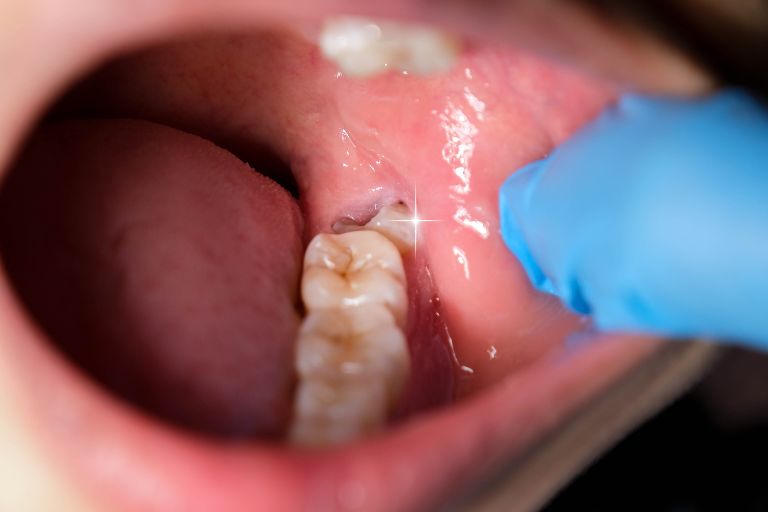

親知らずは生え方などによって、歯ぐきが腫れたり、周囲の歯まで虫歯になったりとトラブルが起こりやすい歯です。

多くは10代後半〜20代前半に生え始めますが、他の歯より遅れて出てくるため、スペースが足りずに斜めに生える、途中までしか歯が出てこない、歯茎の中に埋まるといったことが起こりがちです。

親知らずや隣の歯が虫歯になった

親知らずは、一番奥に生えるので歯ブラシで磨きにくく、虫歯になりやすいです。磨き残しが多いと隣の歯まで虫歯が広がることも。

虫歯が進行すると治療が大きくなり、抜歯になることもあります。

親知らずの周囲に細菌が増えると、歯ぐきが腫れる「智歯周囲炎」になる場合もあります。炎症を繰り返すと顎骨にまで広がるリスクもあるため、抜歯を検討することが一般的です。